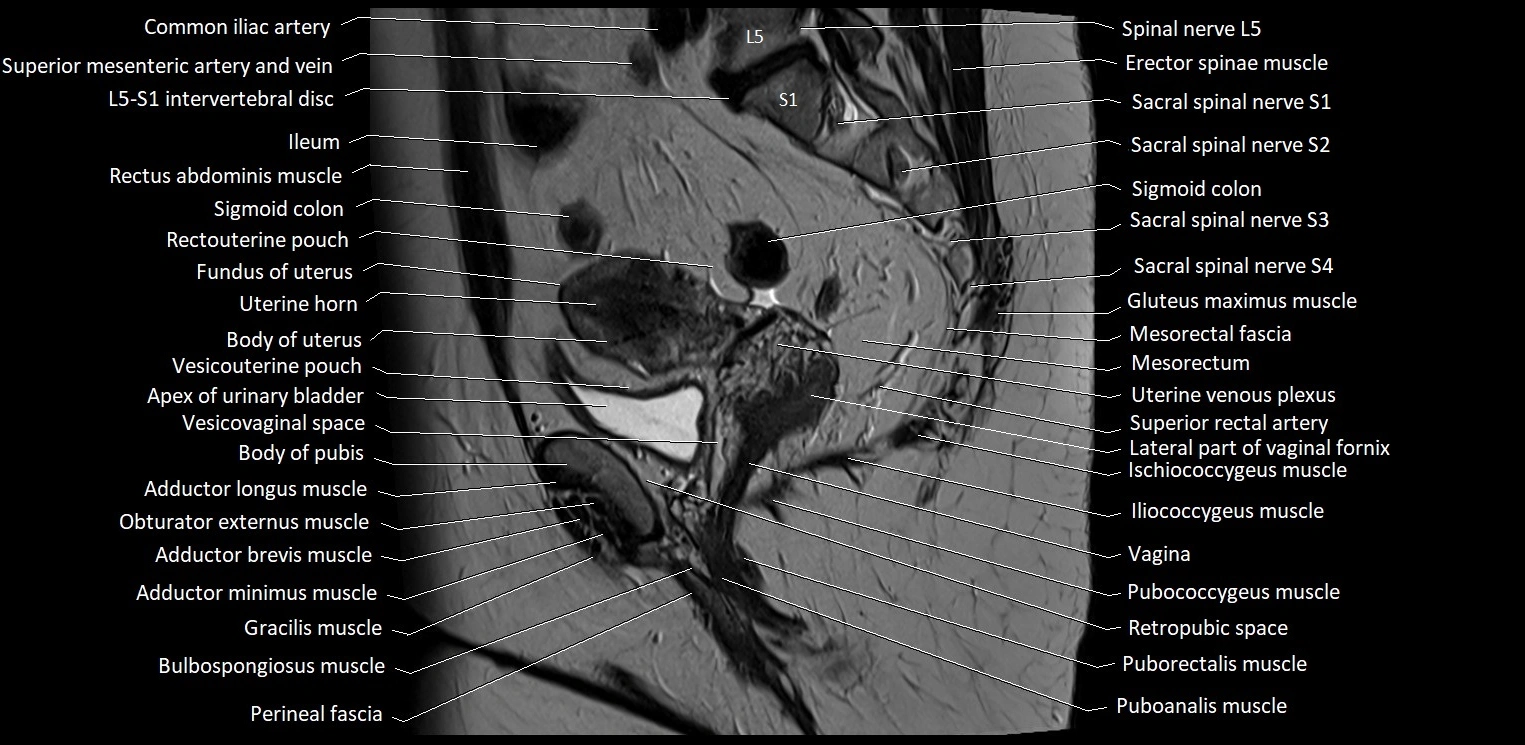

- Apex of urinary bladder

- Body of pubis

- Body of uterus

- Coccyx

- Erector spinae muscles

- External iliac vein

- Fundus of urinary bladder

- Fundus of uterus

- Gracilis muscle

- Ileum

- Iliococcygeus muscle

- Iliopsoas muscle

- L5–S1 Intervertebral disc

- Mesorectal fascia

- Mesorectum

- Obturator externus muscle

- Pubococcygeus muscle

- Puborectalis muscle

- Puboanalis muscle

- Rectouterine pouch (pouch of Douglas)

- Rectum

- Sigmoid colon

- Spinal nerve L5

- Spinal nerve S1

- Spinal nerve S2

- Spinal nerve S3

- Superior rectal artery

- Uterine horn

- Uterine venous plexus

- Vagina

- Vesicouterine pouch

- Vesicovaginal space

- common iliac artery